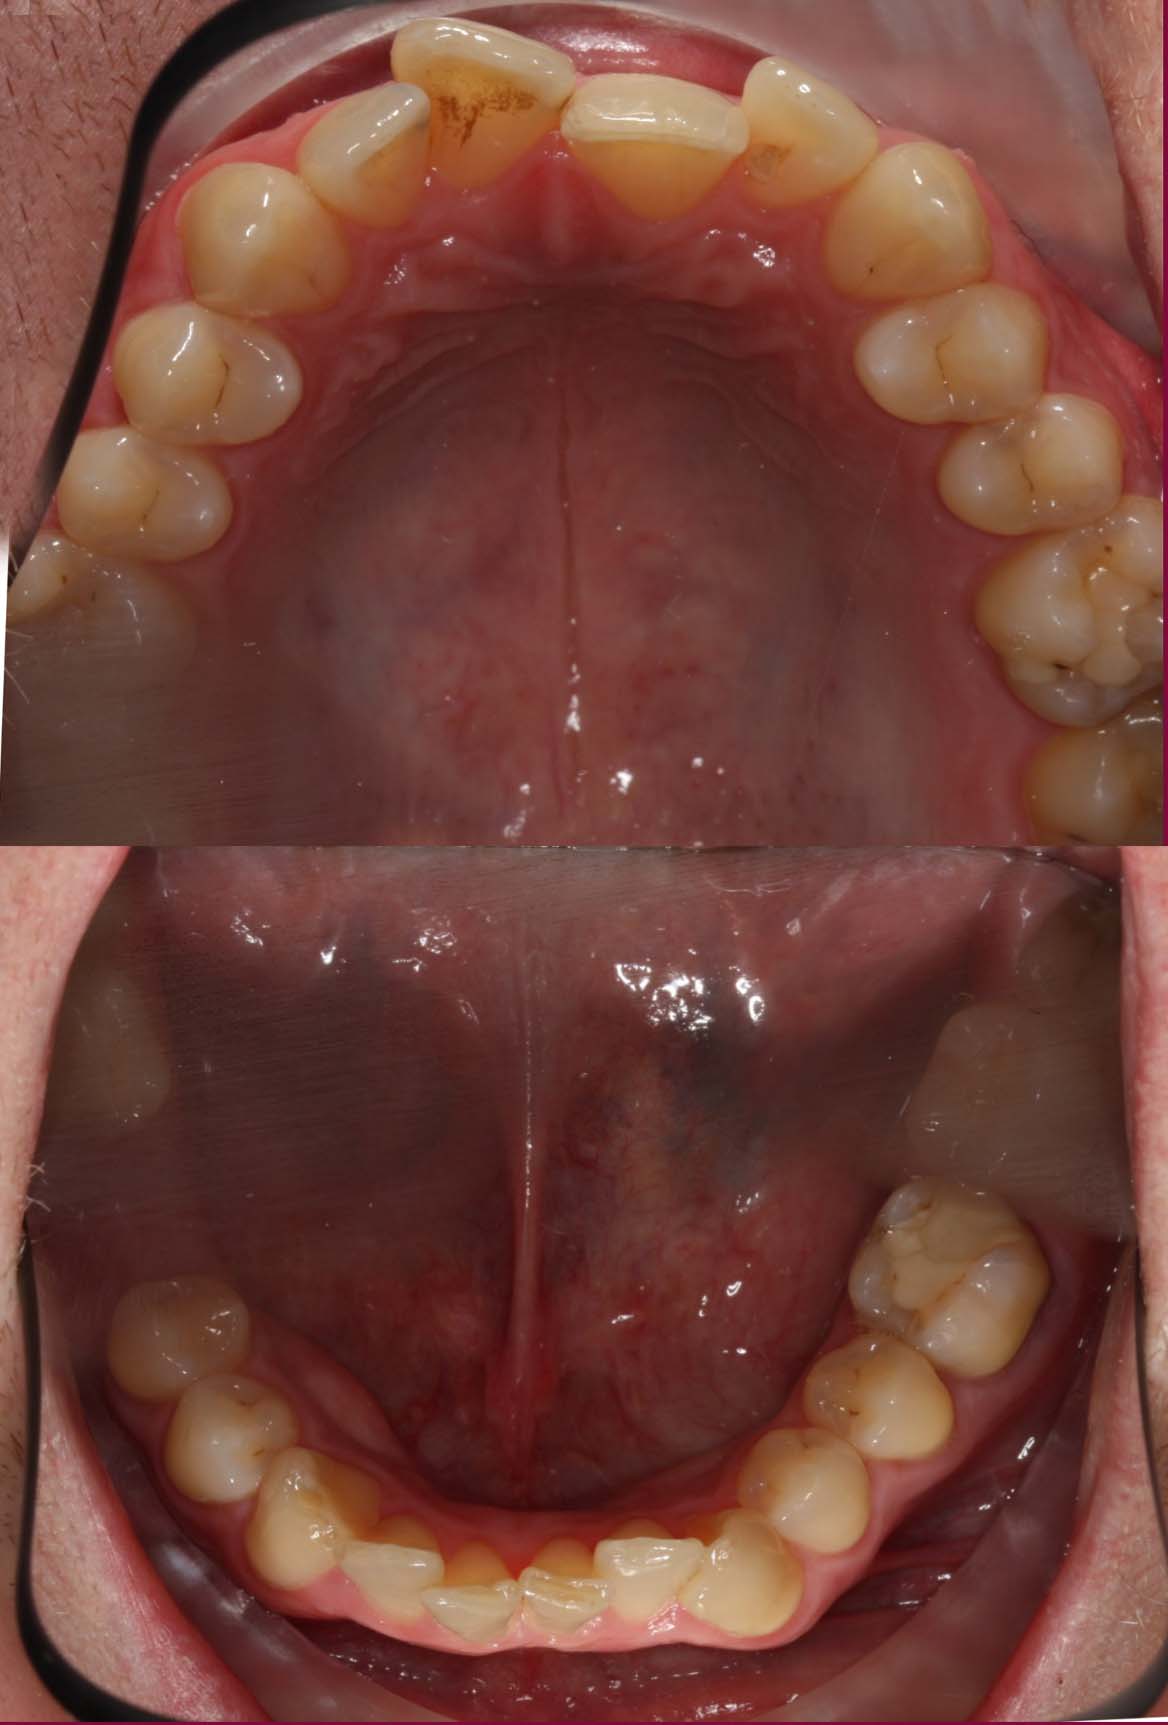

Bei uns können Zahn- sowie Kieferfehlstellungen durch Zahnspangen behandelt werden. Auch Zahnspangen mit weißen Brackets und weißem Draht, die zu einem unauffälligen und dezenteren Erscheinungsbild führen, sind bei uns erhältlich.

Schienen sind oft eine sehr gute Alternative zu festsitzenden Zahnspangen, die wir in Zusammenarbeit mit einem renommierten  Zahntechniker eigens für den Patienten erstellen, um die Zahnfehlstellung zu korrigieren und dem Knirschen entgegenwirken.